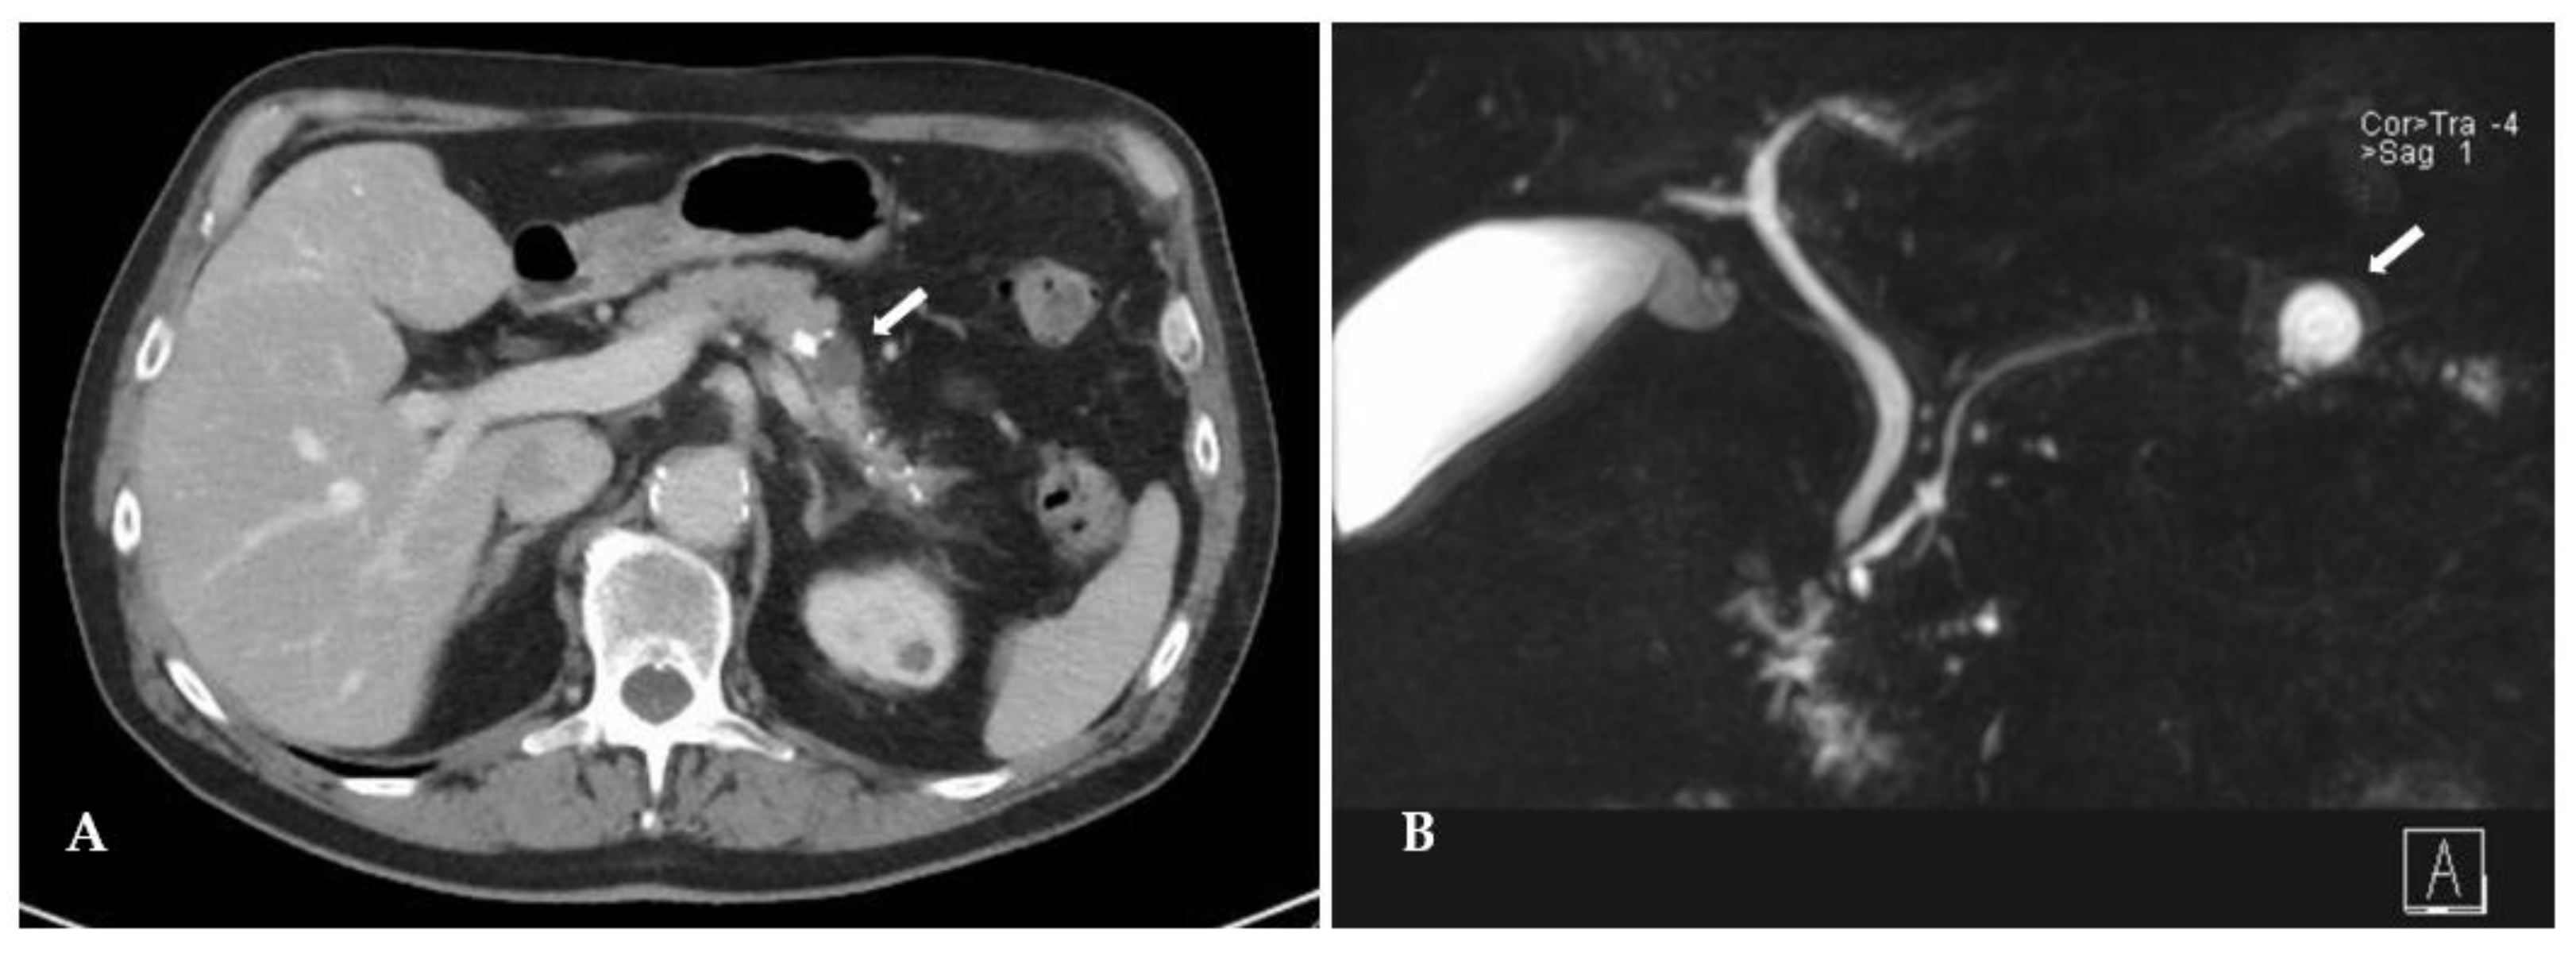

The patient was a 72-year-old man with a body mass index of 25 kg/m² (184 cm, 85 kg) referred to our hospital for evaluation of a cystic lesion of the pancreatic body, incidentally detected on a CT-scan 2 years ago during evaluation of an ulcus of the aortic arch. The patient suffered intermittent episodes of nausea and postprandial epigastric pain, accompanied by 10 kg weight loss over the last 6 months. The lesion grew from 10 mm to 22 mm over 2 years and developed solid enhancing components, seen on CT, MRCP and on endoscopic ultrasonography. Calcifications were present just proximal to the cyst as well as in the pancreatic tail distal to it, which were not present in the pancreatic head (Figure 1). There was no history of alcohol abuse, hypercalcemia, however the patient admitted having been an active chain smoker for over 40 years. Diabetes mellitus was diagnosed two years ago. Tumor markers CA19-9 and CEA were within normal range. The lesion was suspected to be either a side-branch IPMN with worrisome features or a pseudocyst in chronic pancreatic tail pancreatitis. Because of a positive family history for pancreatic cancer the patient declined a wait-and-watch management and was scheduled for a distal pancreatectomy with splenectomy, and a written informed consent was obtained.

Figure 1. Preoperative CT (A) and MRCP (B) images of a cystic lesion (white arrow) in the pancreatic body.